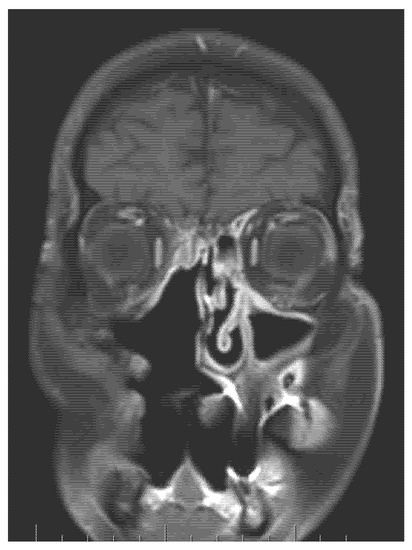

Highly Aggressive Osteosarcoma of the Ethmoids and Maxillary Sinus-A Case of Successful Surgery and Proton Beam Radiotherapy in a 65-Year-Old Man

2. Case Report (Observation)